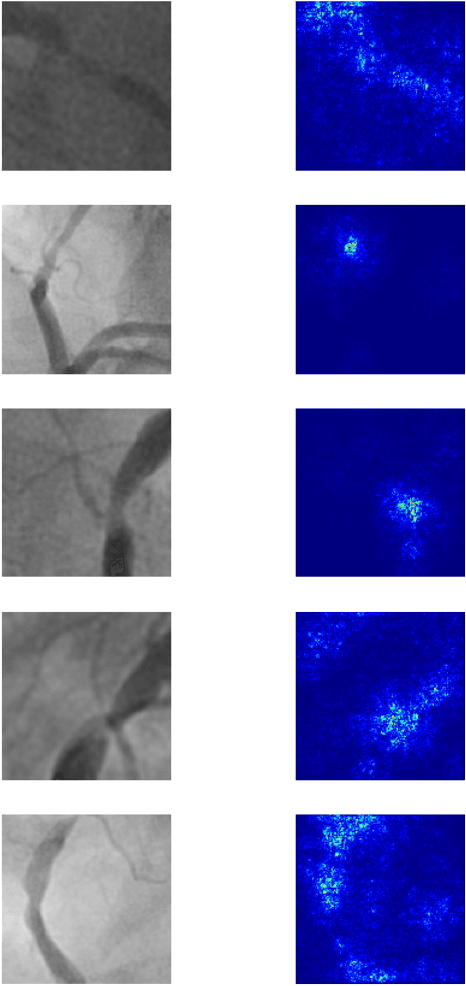

Abstract:Coronary heart disease (CHD) is the leading cause of adult death in the United States and worldwide, and for which the coronary angiography procedure is the primary gateway for diagnosis and clinical management decisions. The standard-of-care for interpretation of coronary angiograms depends upon ad-hoc visual assessment by the physician operator. However, ad-hoc visual interpretation of angiograms is poorly reproducible, highly variable and bias prone. Here we show for the first time that fully-automated angiogram interpretation to estimate coronary artery stenosis is possible using a sequence of deep neural network algorithms. The algorithmic pipeline we developed--called CathAI--achieves state-of-the art performance across the sequence of tasks required to accomplish automated interpretation of unselected, real-world angiograms. CathAI (Algorithms 1-2) demonstrated positive predictive value, sensitivity and F1 score of >=90% to identify the projection angle overall and >=93% for left or right coronary artery angiogram detection, the primary anatomic structures of interest. To predict obstructive coronary artery stenosis (>=70% stenosis), CathAI (Algorithm 4) exhibited an area under the receiver operating characteristic curve (AUC) of 0.862 (95% CI: 0.843-0.880). When externally validated in a healthcare system in another country, CathAI AUC was 0.869 (95% CI: 0.830-0.907) to predict obstructive coronary artery stenosis. Our results demonstrate that multiple purpose-built neural networks can function in sequence to accomplish the complex series of tasks required for automated analysis of real-world angiograms. Deployment of CathAI may serve to increase standardization and reproducibility in coronary stenosis assessment, while providing a robust foundation to accomplish future tasks for algorithmic angiographic interpretation.